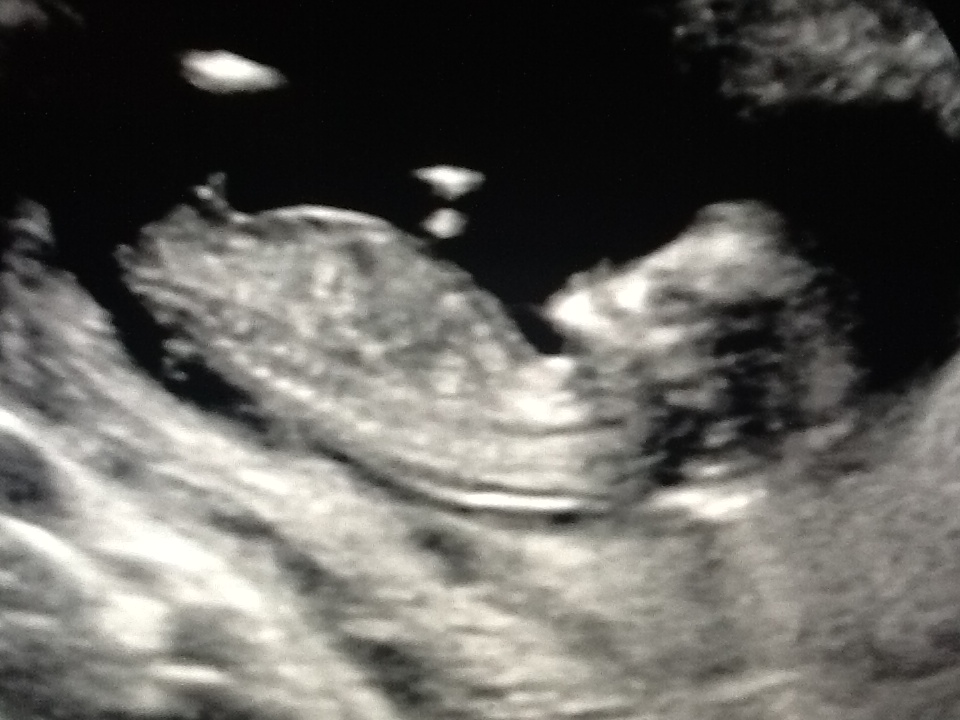

12 WEEKS 2 Days - Can anyone help me guess??

So excited to post here and I hope I've got the right pictures, I've honestly got no idea, so would really appreciate your guesses. I'm 14 weeks now and have been obsessing the last couple of nights :think: I'm having another scan in 2weeks but just can't wait! Either way, the babe looks lovely and healthy so far, for which I'm grateful.

I've attached 2 horizontal shots and 1 that I think is the potty shot, even though I know it can be too early for that.